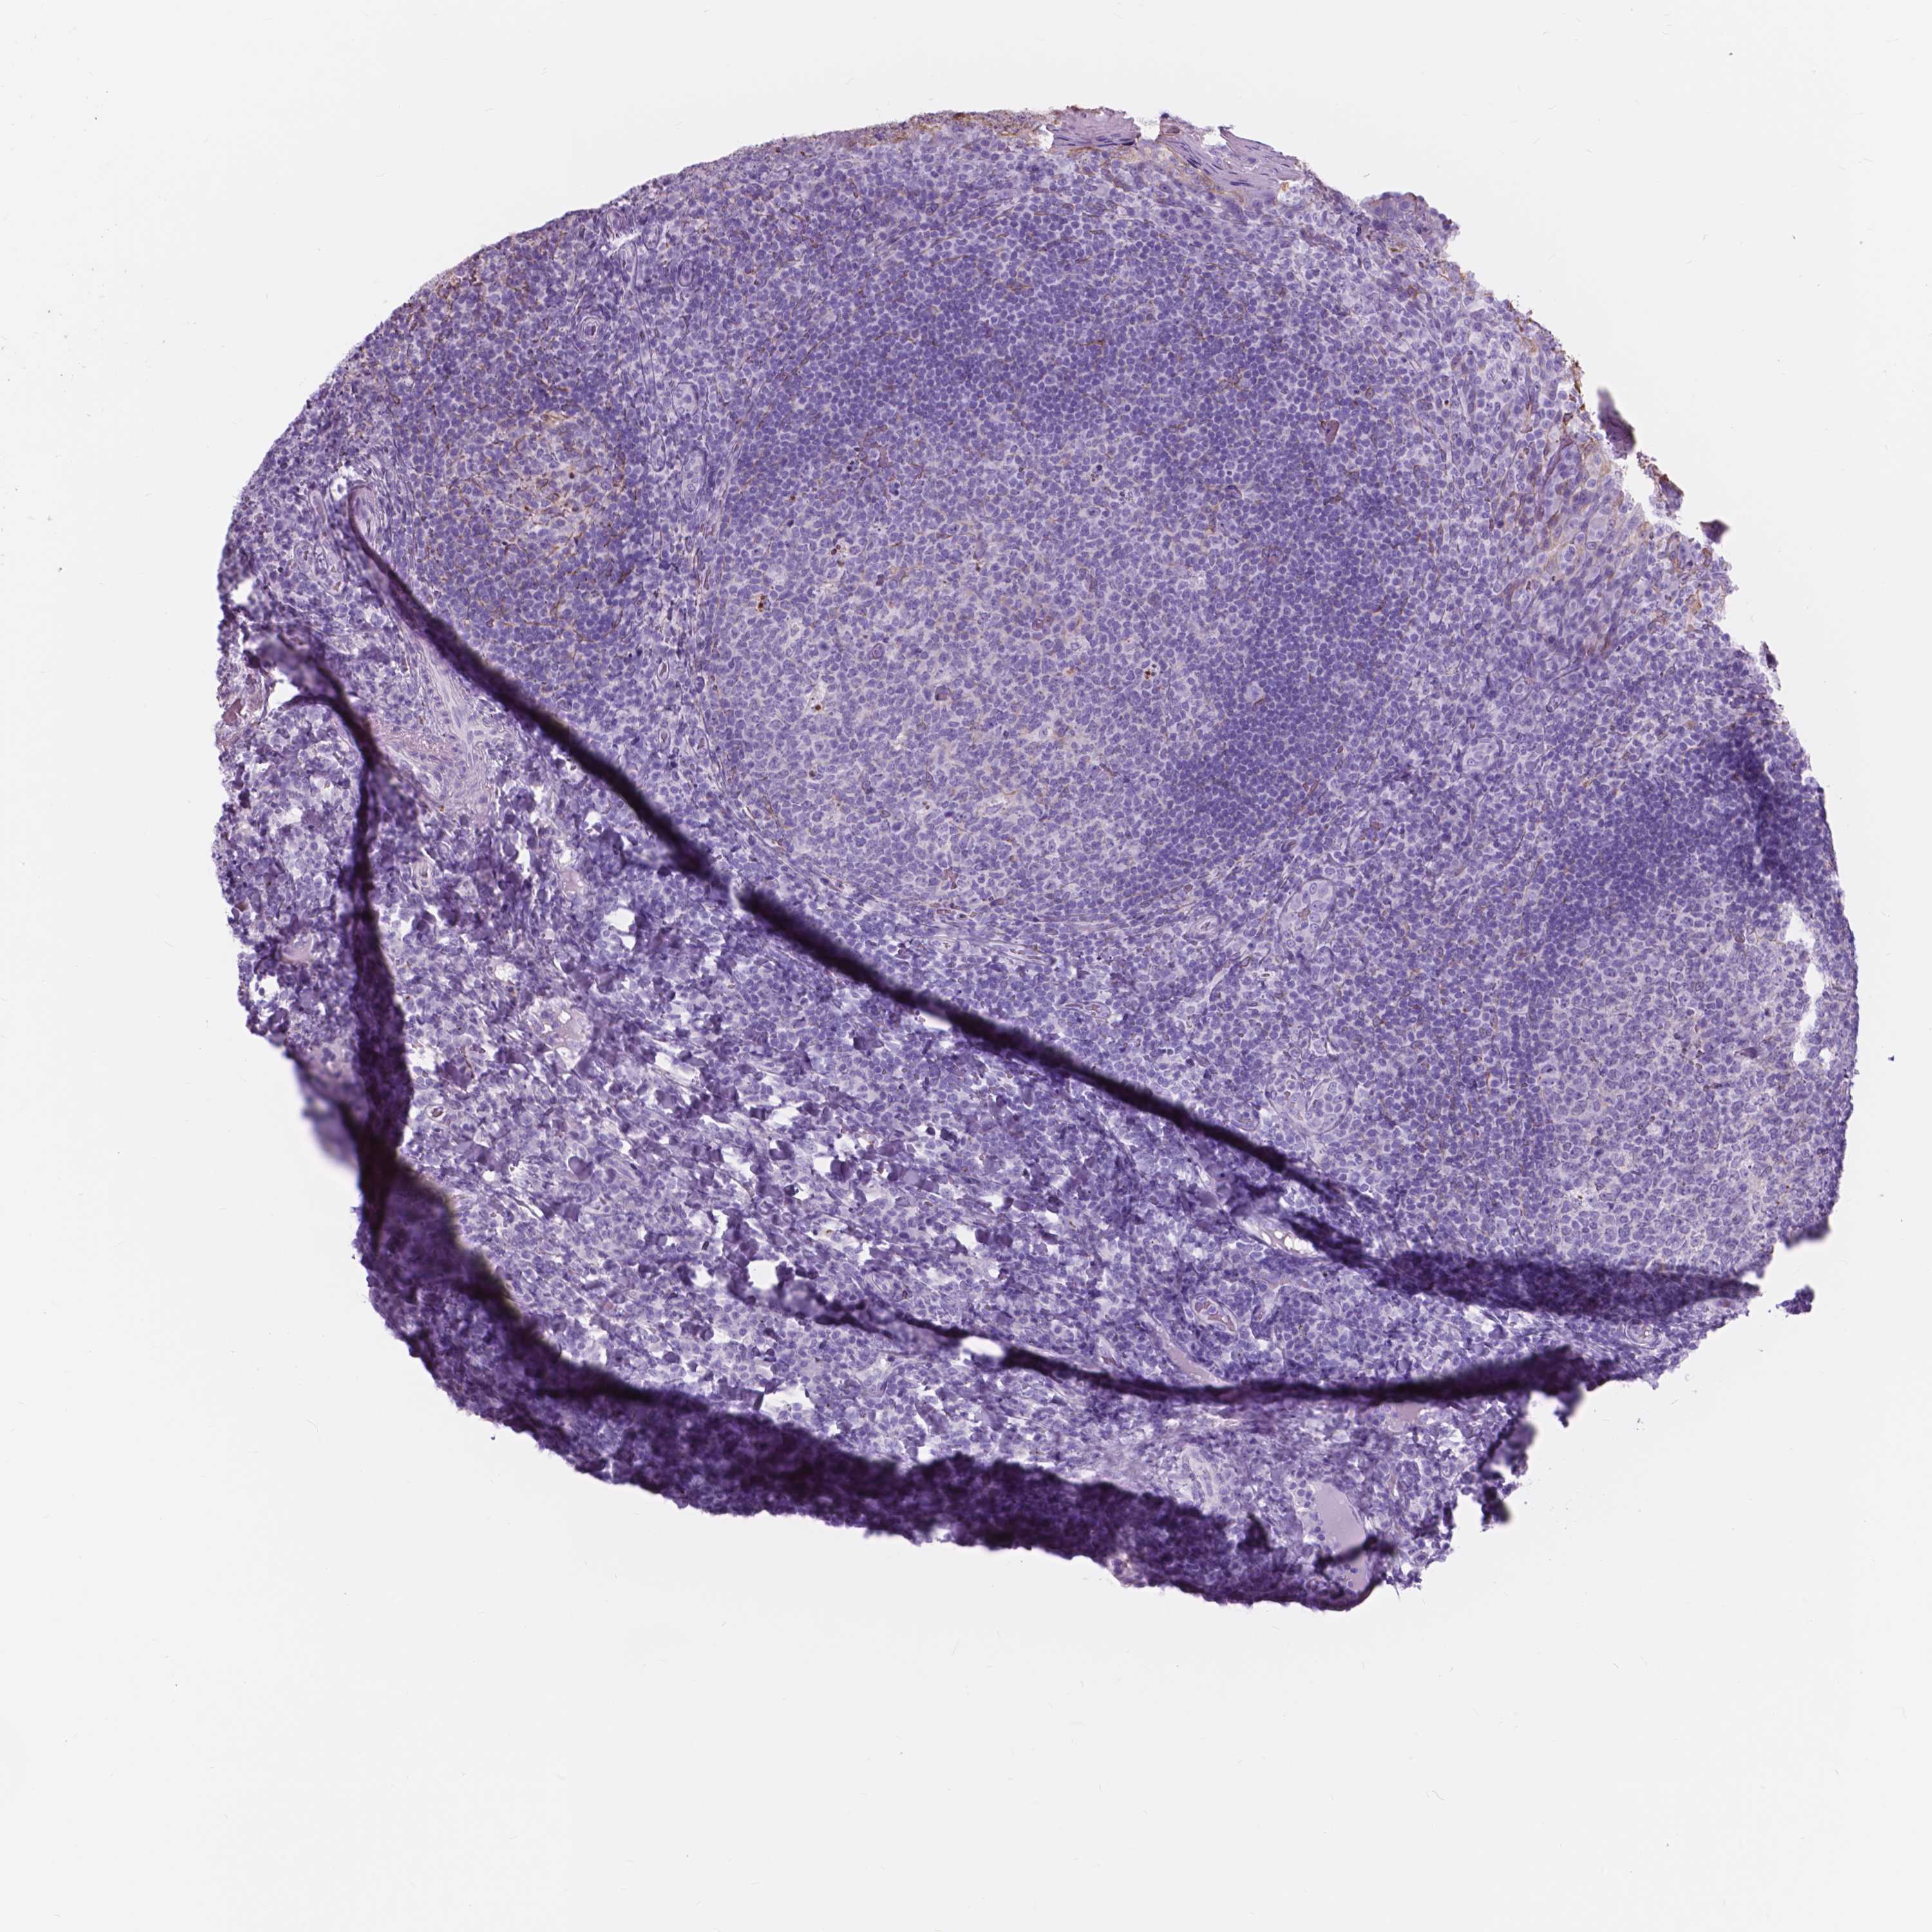

FXYD2